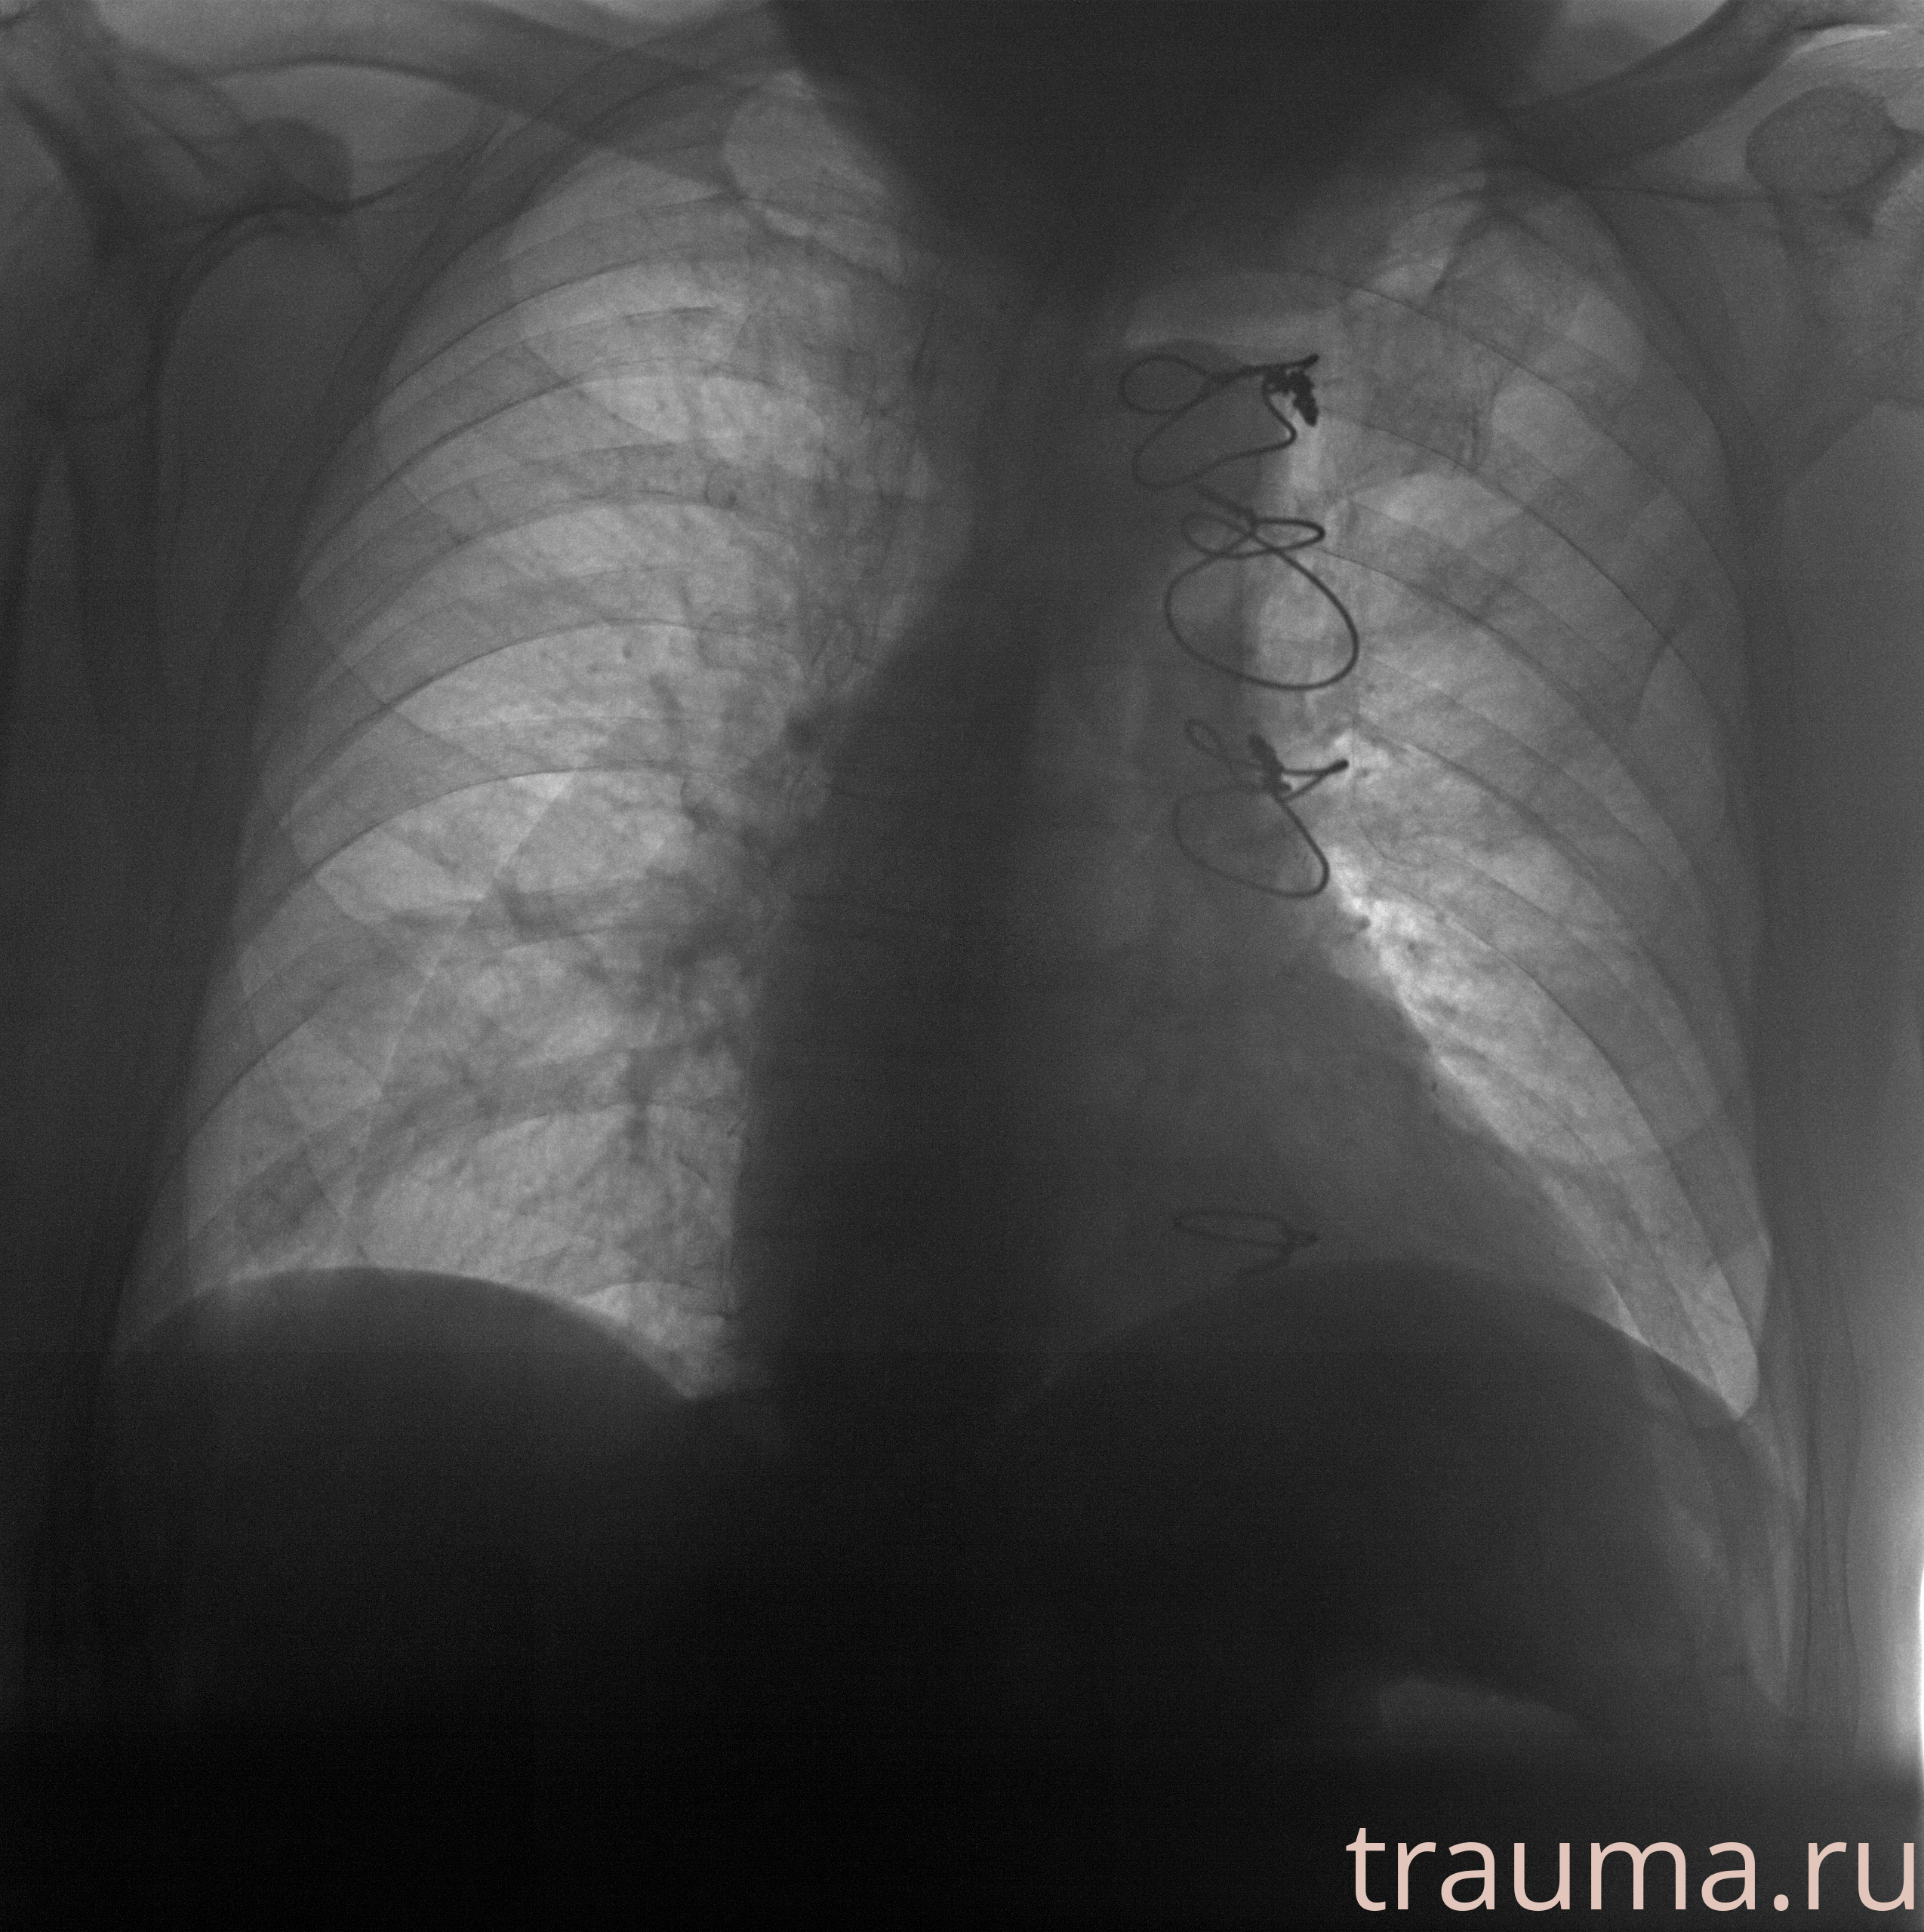

Рентген на дому: по вашему адресу приезжает врач-рентгенолог, травматолог-ортопед с мобильным рентгеновским аппаратом, проводит диагностику травмы или заболевания, делает необходимые рентгенограммы, дает рекомендации по дальнейшему лечению. Получить качественные снимки в домашних условиях возможно благодаря уникальной методике, разработанной МосРентген Центром для института  Склифосовского

при переломе шейки бедра и пневмонии от компании МосРентген Центр - партнера Института имени Склифосовского